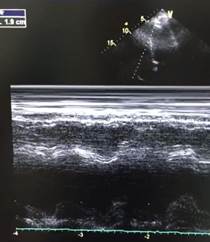

A las 48 horas de ingreso en UCI presenta de forma súbita deterioro hemodinámico e hipoxemia refractaria que no mejoraba, a pesar de encontrase en decúbito prono y con parámetros ventilatorias adecuados. Se procedió a realizar ecocardiograma (Fig. 1) que reporta ventrículo izquierdo con  diámetros conservados, motilidad conservada, función sistólica FEVI 61% por Simpson, cavidades derechas dilatadas VD 4.2 basal,  TAPSE 1 cm, onda S 0.07 m/seg, vena cava 1.7 cm, en el eco doppler llenado diastólico con patrón normal, insuficiencia tricuspidea moderada Vmax 3.2 m/seg, PSP aproximada 45 mmhg, disfunción sistólica del VD, dilatación de cavidades derechas.

Figura 1. Ecocardiograma previo a tratamiento fibrinolítico. A Disfunción sistólica de VD con TAPSE 1, B Insuficiencia tricúspidea con Vmax 3,2 m/seg , C Dilatación de cavidades derechas